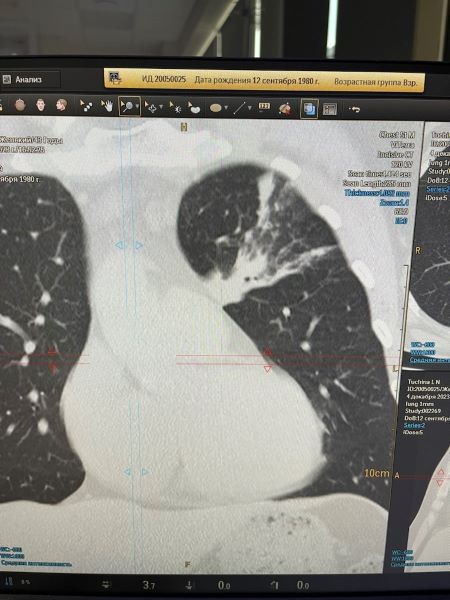

Левосторонняя полисегментарная пневмония

Самостоятельно обратился в клинику ВиТерра для обследования органов грудной клетки на МСКТ ( мультисрезовый Филипс ).

Результаты пациент получил сразу же после сканирования и на приёме врача-терапевта клиники получил соответствующее лечение.